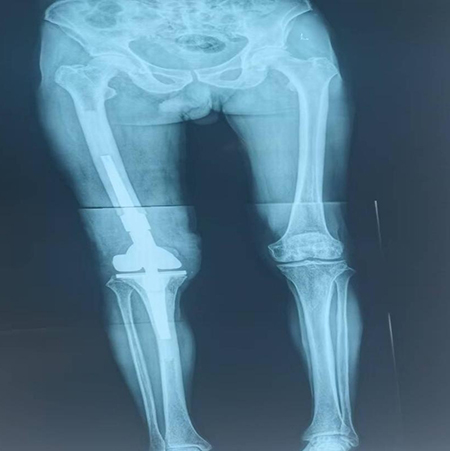

膝关节置换术后假体周围骨折,假体松动

术后双下肢全长片